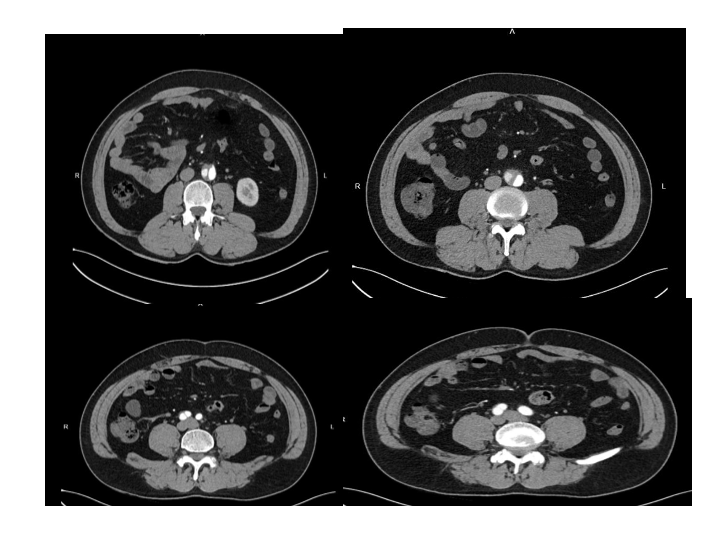

腹部外伤急救